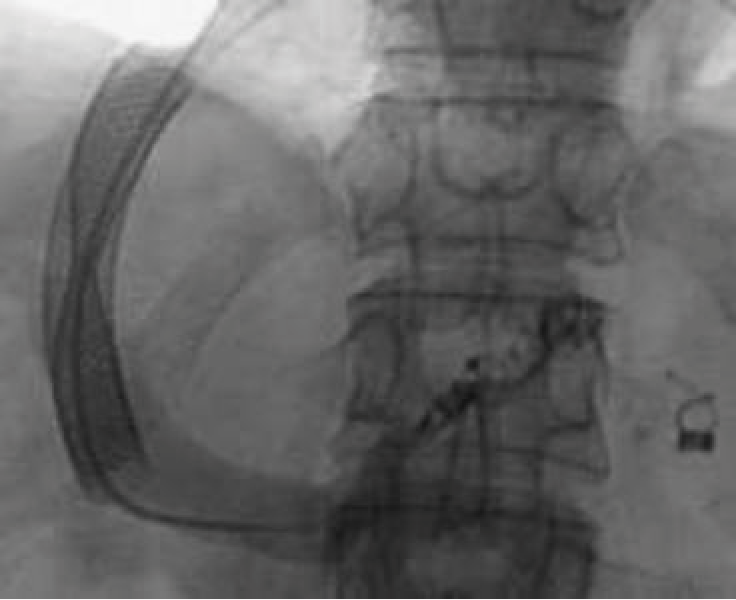

后来,Sze等报道了一种在TIPS支架内平行放置植入支架和球囊可扩张支架的技术。

球囊可扩张支架,这将确定流腔。

(2)有些研究者赞成减小TIP腔的有效直径,而不是完全地阻塞分流。一种经过改良的支架,可以呆有预先确定的分流中部的狭窄,并被放置到现存的支架内,以减少它的有效直径。